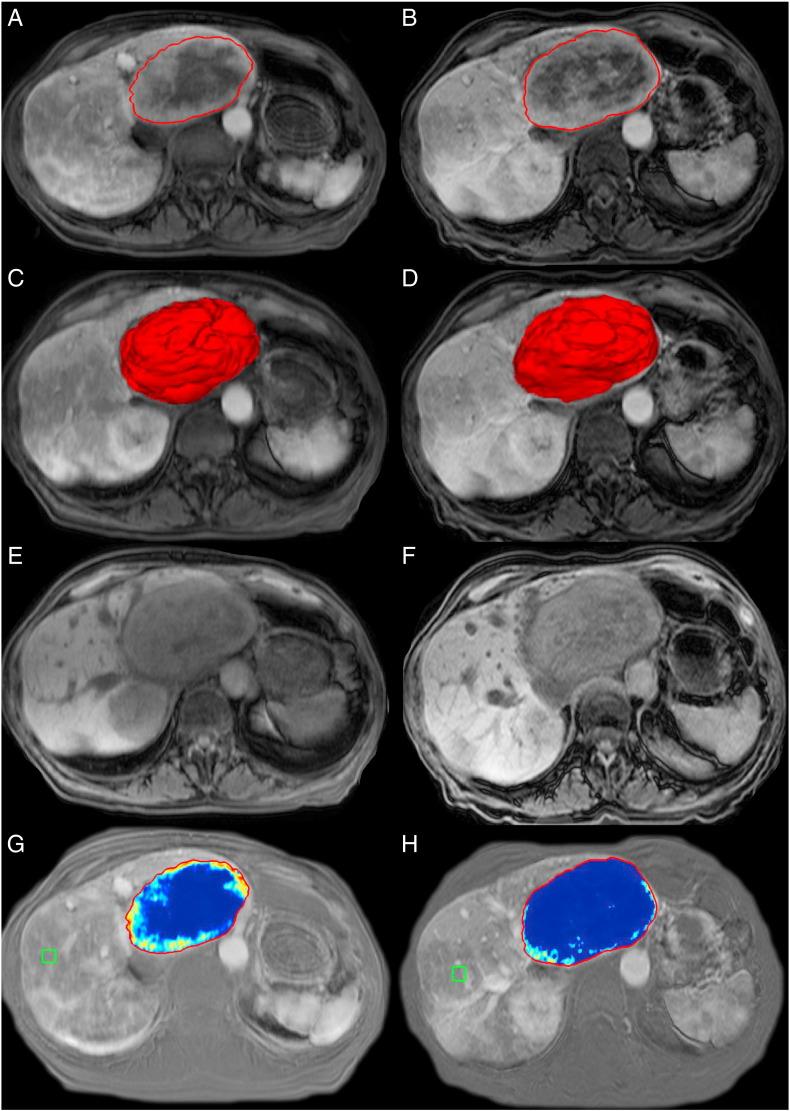

Liver metastases from renal cell carcinoma (RCC) are not uncommon in the course of disease. However, data about tumor response to intraarterial therapy (IAT) are scarce. This study assessed whether changes of enhancing tumor volume using quantitative European Association for the Study of the Liver (qEASL) on magnetic resonance imaging (MRI) and computed tomography (CT) can evaluate tumor response and predict overall survival (OS) early after therapy.

Fourteen patients with liver metastatic RCC treated with IAT (transarterial chemoembolization: n= 9 and yttrium-90: n= 5) were retrospectively included. All patients underwent contrast-enhanced imaging (MRI: n= 10 and CT: n= 4) 3 to 4 weeks pre- and posttreatment. Response to treatment was evaluated on the arterial phase using Response Evaluation Criteria in Solid Tumors (RECIST), World Health Organization, modified RECIST, EASL, tumor volume, and qEASL. Paired t test was used to compare measurements pre- and post-IAT. Patients were stratified into responders (≥65% decrease in qEASL) and nonresponders (<65% decrease in qEASL). OS was evaluated using Kaplan-Meier curves with log-rank test and the Cox proportional hazard model.

Mean qEASL (cm) decreased from 93.5 to 67.2 cm (P= .004) and mean qEASL (%) from 63.1% to 35.6% (P= .001). No significant changes were observed using other response criteria. qEASL was the only significant predictor of OS when used to stratify patients into responders and nonresponders with median OS of 31.9 versus 11.1 months (hazard ratio [HR], 0.43; 95% confidence interval [CI], 0.19-0.97; P= .042) for qEASL (cm) and 29.9 versus 10.2 months (HR, 0.09; 95% CI, 0.01-0.74; P= .025) for qEASL (%).

Three-dimensional (3D) quantitative tumor analysis is a reliable predictor of OS when assessing treatment response after IAT in patients with RCC metastatic to the liver. qEASL outperforms conventional non-3D methods and can be used as a surrogate marker for OS early after therapy.